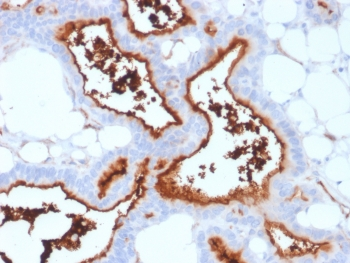

IHC staining of FFPE human prostate carcinoma with CD73 antibody (clone NT5E/2545). HIER: boil tissue sections in pH9 10mM Tris with 1mM EDTA for 10-20 min and allow to cool before testing.

IHC staining of FFPE human pancreatic carcinoma with CD73 antibody (clone NT5E/2545). HIER: boil tissue sections in pH9 10mM Tris with 1mM EDTA for 10-20 min and allow to cool before testing.